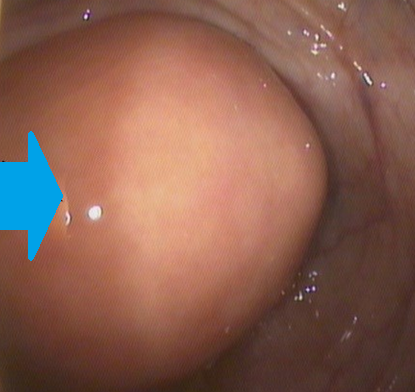

Κολονοσκοπική εικόνα βλεννοκήλης — Υποβλεννογόνια μάζα. Μπλε βέλος — «Σημείο ηφαιστείου» (Ευγενική παραχώρηση Dr. V. Penopoulos)